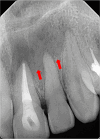

This case report highlights the successful healing of a large periapical lesion through non-surgical root canal retreatment. A 29-year-old male patient presented with a significant radiolucency associated with teeth #21 and #22, initially treated non-surgically. Despite the lesion's size, the treatment, which included thorough canal disinfection and obturation, led to substantial healing. A follow-up cone-beam computed tomography (CBCT) scan after one year confirmed the buccal cortical bone reformation and improvement in the incisive canal area except for the apical region of #21. Subsequently, root canal retreatment was performed for #21. Complete healing was achieved after two years, demonstrating that even extensive periapical lesions can be effectively treated with non-surgical endodontic retreatment, avoiding invasive surgical intervention.